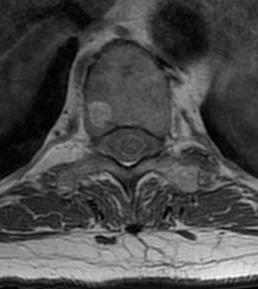

MRI

Usually bright on T1 & T2 images because of fat content